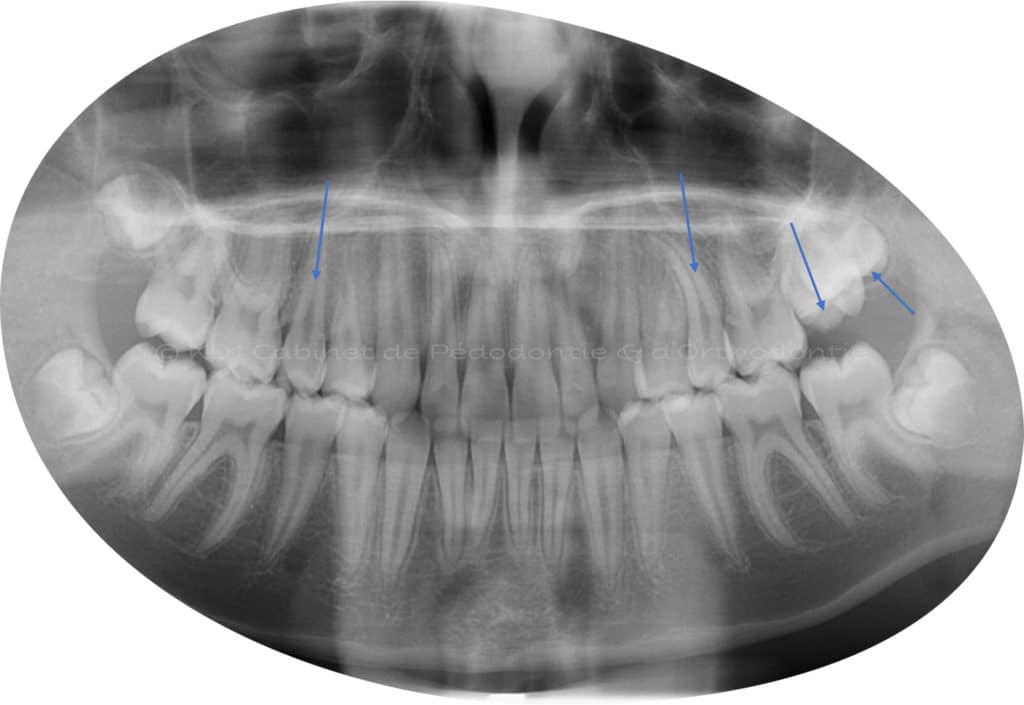

Cas #1 – Traitement avec des bagues, deuxièmes prémolaires et dent de sagesse supérieures ectopiques.